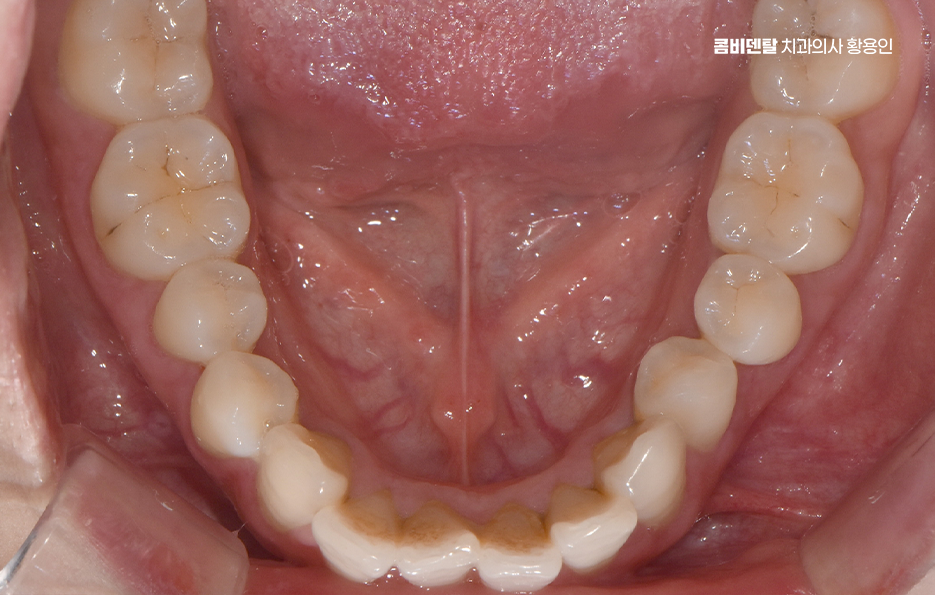

돌출입 팔자주름 교정 치아를 어떻게 움직이느냐에 따라 얼굴 인상이 달라지는 것인데 돌출입 교정은 일반적으로 소구치 네 개를 발치한 후, 앞니를 뒤쪽으로 밀어넣고 악궁을 재배열하는 방식으로 진행되며 앞니가 뒤로 이동하고 자연스럽게 입술이 들어가게 되고, 입술 돌출도가 줄어들면서 얼굴이 전반적으로 부드럽고 조화로운 느낌으로 바뀔 수 있어요

옆모습에서 입이 덜 나와 보이고, 턱선이 또렷해지는 것도 이런 원리에서 비롯되며 치아 배열 자체는 물론이고, 입술과 턱 근육의 균형이 맞춰지기 때문에 얼굴 인상이 부드럽고 안정적으로 바뀌는 거예요.

돌출입 팔자주름 교정 그럼 팔자주름은 어떻게 변하느냐는 질문도 많은데 돌출입이 있는 사람들은 입 주변 근육에 지속적으로 긴장이 들어가기 때문에 팔자주름이 더 도드라져 보이는 경우가 많고 입술이 앞으로 나와 있다 보니, 코 밑에서부터 입꼬리로 이어지는 주름이 더 깊게 파이고, 표정이 굳어 보일 수도 있었어요.

그런데 치아를 뒤로 이동시키면서 입술이 안쪽으로 정리되면, 입 주변의 긴장도 줄어들게 되고, 자연스럽게 팔자주름이 완화되는 효과가 생기는 것이며 물론 주름 자체를 없애는 시술처럼 극적인 효과는 아니지만, 돌출이 줄어들면서 팔자주름이 덜 도드라져 보이고 얼굴의 입체감이 개선되는 건 분명한 변화라고 볼 수 있어요